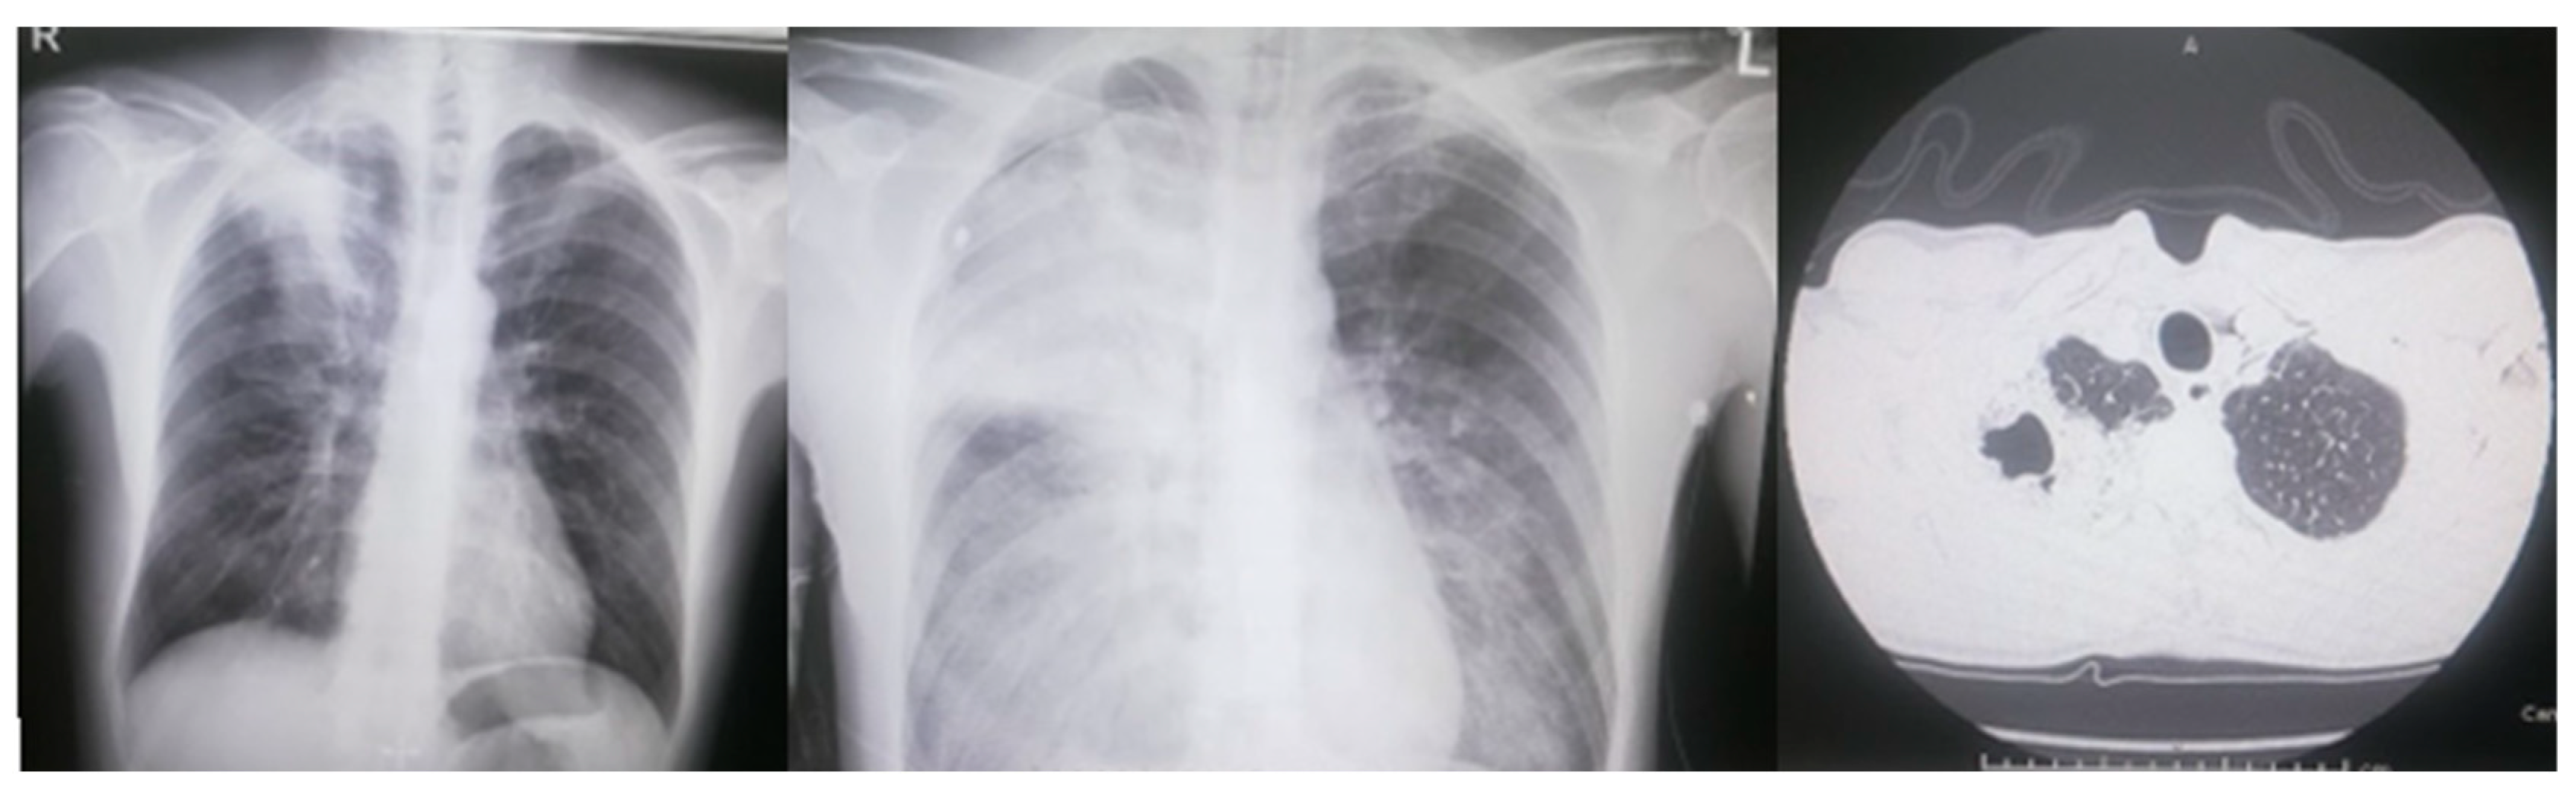

| Reference Site (Year) | Exposure | Sex Age | Smoke Alcohol | Symptoms on admission | Radiology | WBC (/µL) CRP (mg/dL) PCT (ng/mL) | Positive colture for PA Other Infection | Antibiotic Therapy | Course and Outcome |

|---|---|---|---|---|---|---|---|---|---|

| Huhulescu et al [28] Austria (2010) | Hot tub water | F 49 | Yes - | Cough Pleuritic chest pain | Left lung infiltration | WBC 3 940 CRP 38.1 | Respiratory sample Blood |

|

| Okamoto et al [29] Japan (2011) | Water in rearing beetles cage | F 39 | Yes Yes | Cough Pleuritic chest pain Hemoptysis Dyspnea Diarrhea | Right upper consolidation Pleural effusion | WBC 21 500 CRP 6.61 | Respiratory sample Blood Pleural fluid |

| Kunimasa et al. [30] Japan (2012) | Washrooms, bathroom in care facility | M 25 | Yes - | Cough Fever Right back pain Hemoptysis | Right upper consolidation, cavitation | WBC 7 800 CRP 14 | Respiratory sample |

| Gharabaghi et al. [31] Iran (2012) | Not known exposure | M 26 | No - | Cough Fever Bone pain | Left upper consolidation, cavitation, left lower lobe mass with necrosis | WBC normal | Respiratory sample Lung biopsy Klebsiella pneumoniae |

| - |

| Fujii et al. [32] Japan (2012) | Not known exposure | M 29 | No | Fever Right back pain | Right upper consolidation, cavitation | WBC 26 400 CRP 20 | Respiratory sample Blood |

| Takajo et al. [33] Japan (2013) | Not known exposure | F 50 | - - | Cough Fever Right back pain Dyspnea Hemoptysis | Right upper lobe consolidation Pneumothorax | WBC 2 100 | Respiratory sample Blood |

| Campos et al. [34] Brazil (2014) | Metalworking fluid | M 44 | Yes - | Cough Fever Right back pain Hemoptysis | Right upper and lower consolidation Left consolidation | WBC 2 880 | Respiratory sample Blood |

| Woods et al. [35] USA (2017) | Home humidifier water | M 30 | No No | Cough Fever Right back pain Weight loss | Right upper consolidation, cavitation | WBC 11 300 | Respiratory sample |

| Su et al. [36] Taiwan (2018) | Not known exposure | F 39 | - | Cough Fever Dyspnea | Bilateral patchy infiltrates | WBC 810 | Respiratory sample Blood Influenza A(H1N1)pdm09 |

| Wang et al. [37] China (2019) | Not known exposure | M 25 | No No | Cough Dyspnea Hemoptysis Brain abscess | Multiple right upper and lower consolidations Pleural effusion | WBC 390 PCT 100 | Respiratory sample Blood |

| Dong et al. [38] China (2019) | Not known exposure | M 1 | No No | Cough Fever Dyspnea Hemoptysis Bloody pleural effusion | Right middle and lower lobe consolidation, cavitation Pleural effusion | WBC 41 780 CRP 102 PCT 4.49 | Respiratory sample Pleural fluid Influenza A |

| Wang et al. [39] China (2019) | Not known exposure | M 67 | Yes (past) - | Cough Fever Dyspnea | Right upper consolidation, cavitation | WBC 20 360 | Respiratory sample Acinetobacter baumanii |